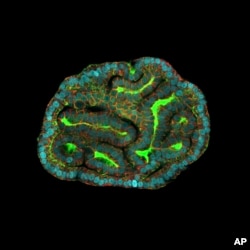

This microscope image provided by researchers in March 2024 shows an intestinal organoid with its distinctive 'bud' structure, created from cells collected from amniotic fluid.(Giuseppe Calà, Paolo De Coppi, Mattia Gerli via AP)